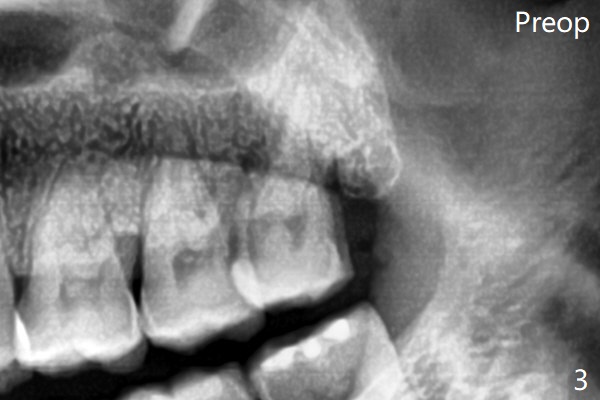

The bone density is high post #1 extraction (Fig.6 (left panel)), related to difficult removal (DB root tip fracture). It appears that bone graft at #16 (^) remains in place 15 months postop.